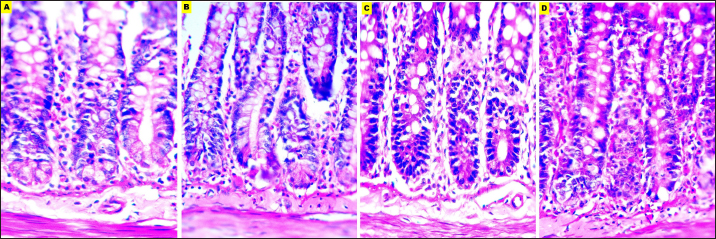

Fig. 7. Microphotographs of Hematoxylin and eosin-stained small intestine sections preserved in different fixatives included, formalin 10% (A), NBF (B), formalin 4% (C), and EZAT solution (D) at 400x magnification.

The overall structural evaluation revealed excellent microscopic appearance with EZAT slides across all types of tissues, characterized by less tissue disintegration, fine cellular details, sufficient nuclear staining, and improved morphological presentation, grades for this parameter were between 4.28 and 4.14 in the kidney and brain slides, which is significantly better than formalin 10 % and NBF (Figs. 47; Table 1). These results suggest that EZAT provides better tissue preservation and staining quality compared with traditional common fixatives.

The overall structural evaluation revealed excellent microscopic appearance with EZAT slides, these observations corresponded with Wester et al. (2003), Bonds et al, (2005), Lykidis et al. (2007), Jensen et al. (2010), and Mori et al. (2015) findings in different zinc-containing formulas compared with NBF, formalin 4% and 10 % fixatives.